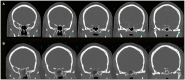

Background: The efficacy and safety of radiosurgery led to paradigm shift in the management of cavernous sinus meningiomas. Nevertheless, patients are still significantly affected by cranial nerve deficits related to the mass effect of these tumors. Our management strategy involves the combination of a functional surgical decompression followed by radiation therapy. Methods: We reviewed a single institution's cohort of patients who underwent endoscopic endonasal decompression (EED) for symptomatic meningiomas primarily involving the cavernous sinus (CS) from 2010 to 2016. The preoperative neuro-ophthalmological exam was compared to the 1- and 6-month postoperative exams. The patient's length of hospital stay, complications, and radiological and clinical follow-up were noted. Results: A total of 17 patients underwent EED for CS meningiomas that fit our radiological criteria. The final outcome at the 6-month visit showed five patients (62.5%) with normalization of deficit and three patients (37.5%) with partial improvement of the CNII deficit. Out of the 12 patients who had cavernous sinus cranial nerves (CSCN) deficits, the final outcome at the 6-month visit showed four patients (33.33%) with normalization of deficit, seven patients (58.3%) with partial improvement, and one patient (8.33%) with no improvement. There were no intraoperative complications. Conclusion: The EED for CS meningiomas is a valuable technique when addressing acute/subacute CNII and CSCN deficits. This conservative surgical approach showed good functional outcomes, low morbidity, and low complication rates. However, it does not exempt the need for radiosurgery/radiation therapy for control of tumor growth.